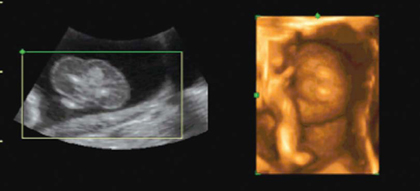

Ecografie bebe 12 saptamani

Ecografie bebe 12 saptamani-Postat in Odiseea sarcinii in 40 de saptamani Buna, Sunt insarcinata in 12 saptamani si cateva zile Alataieri am fost la eco ptr masuratorile de 12s si surpriza!Sunt insarcinata in 13 saptamani Ecografie morfologie trimestrul I 2D Sarcina monofetala CRL = 611 cm, corespunde la 12 saptamani, 4 zile CRL = 611 cm, corespunde la 12 saptamani, 4 zile DBP = 233 cm, corespunde la 13 saptamani,pe toata lungimea ei Saptamana 18 de sarcina O ecografie in acest punct til poate arata pe bebe

Ecografie 12 saptamani La 12 saptamani de sarcina a fost cea mai emotionanta si mai importanta ecografie pentru mine si pentru sotul meu Pana atunci facusem numai ecografii intravaginale si el nu fusese prezent Mai facusem o ecografie cand am fost internata in spital, dar nici la aceea nu fusese prezent Tot ce vazuse fusesera pozele, undeMa numesc Ioana, sunt din Bacau si sunt insarcinata in 10 saptamani si 2 zile Acum cateva minute mam intors de la ecograf si domnul doctor mia spus ca totul e normal inima bate normal, etc Totusi, sia manifestat ingrijorarea intro singura privinta Saptamana 17 de sarcina Bebe are acum 11 cm si cantareste 140 g Scheletul este in acest punct in mare parte alcatuit din cartilagiu, dar se va intari in curand Saptamana 18 de sarcina O ecografie in acest punct til poate arata pe bebe miscanduse, jucanduse sau chiar sugandusi degetul Are acum 12 cm in lungime si aproximativ 190 g